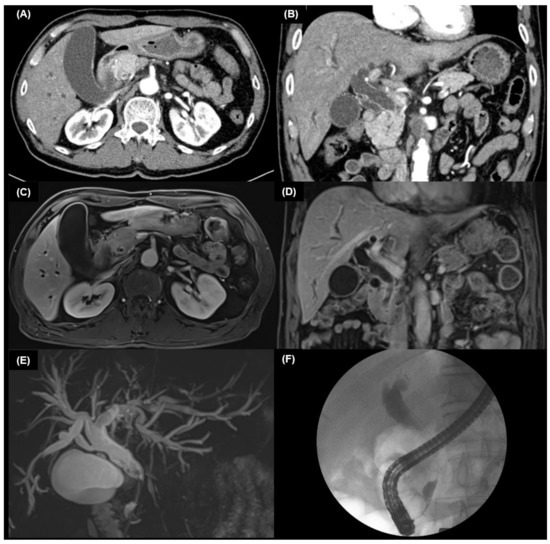

4.2. Multidetector Computed Tomography

4.2.1. Intrahepatic Cholangiocarcinoma

4.2.2. Extrahepatic Cholangiocarcinoma

4.3. MRI and MRCP